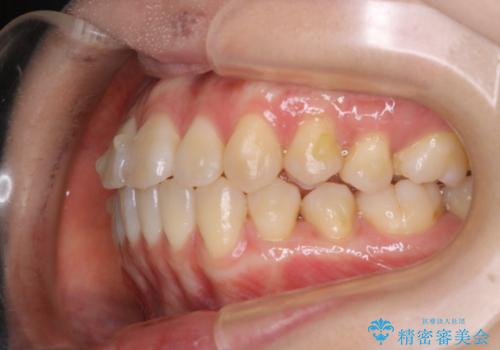

- 前歯のがたつきが気になるとご相談にいらした方です。右側前歯部のクロスバイトの他、左側にもシザーズバイトが認められたため、インビザラインにて治療を行いました。出産直後のため、ご自身の時間がなかなか取れないとの事で、最小限の来院回数で治療を勧められるように計画しました。

患者様ご自身で使用時間をしっかり管理して頂くことを条件に、最低限の来院回数で治療を進めていきました。20時間以上の使用を厳守して頂けたことで、少ない来院回数にて治療を終了することが出来ました。前よりも噛みやすくなったと大変喜んでいただけました。